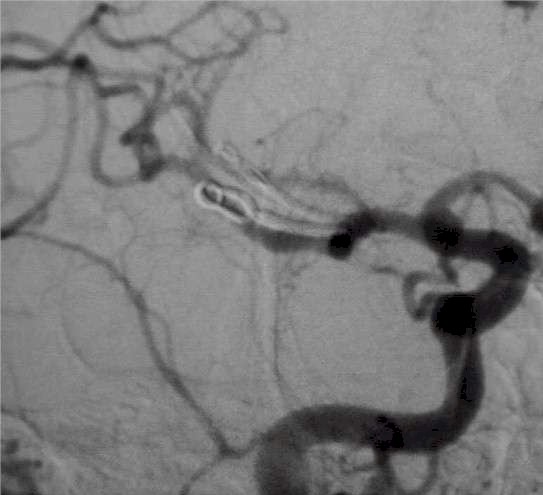

Duplice aneurisma: da un

lato esclusione con clip (freccia gialla), dall'altra con spirali. |